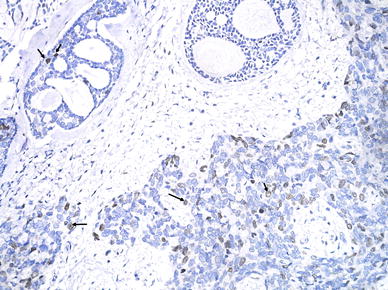

On immunohistochemistry the tumor was diffusely positive for cytokeratin, epithelial membrane antigen and S-100 in both the components. Smooth muscle actin was confined to the abluminal cells in the differentiated component but was negative in the high-grade component. This was interpreted as presence of both epithelial and myoepithelial differentiation in the conventional ACC areas, while there was loss of myoepithelial differentiation in the high grade areas. p53 expression was seen in 20% tumor cells of conventional ACC and was of moderate intensity. However the high-grade component displayed strong nuclear p53 positivity in ~60% of tumor cells. Ki-67 staining showed a cell proliferation index of <10% in conventional ACC and 50% in the high-grade areas (Fig. 4). E-Cadherin and c-kit (CD117) were positive in both the conventional and high-grade areas. Both components had no Her-2/Neu expression.

Fig. 4

Nuclear positivity for Ki67 (arrows) in greater proportion of cells in high-grade component (lower right) as compared to conventional component (upper left) (DAB)